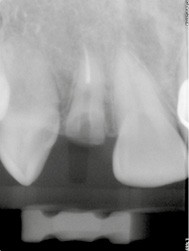

Nous allons décrire, étape par étape, les différents temps cliniques permettant l’élaboration d’un guide chirurgical et la place de la CFAO de la planification à la réalisation du temps chirurgical au travers d’un cas clinique (fig. 1).

L’édentement concerné et l’arcade antagoniste sont enregistrés à l’aide d’une empreinte optique intra-orale (fig. 2) ou d’une empreinte physico-chimique. Cette dernière devra être numérisée avec un scanner de table, nous permettant d’obtenir un fichier STL. L’info-prothésiste modélise alors un wax-up numérique, en veillant à l’intégration de la future restauration prothétique.